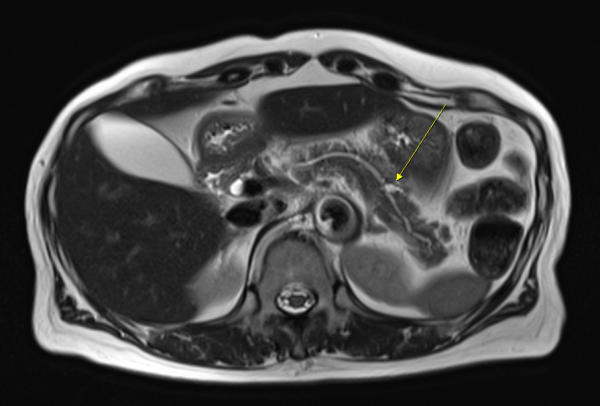

췌장 꼬리(화살표)까지 선명하게 포착한 3.0T MRI 영상[자료 제공 : 그린몰의원]

MRI는 뼈나 가스의 방해를 받지 않고 췌장의 단면을 고해상도로 구현할 수 있어,

초음파로 보이지 않는 미세 췌장염이나 종양, 담석까지 한 번에 찾아낼 수 있다.